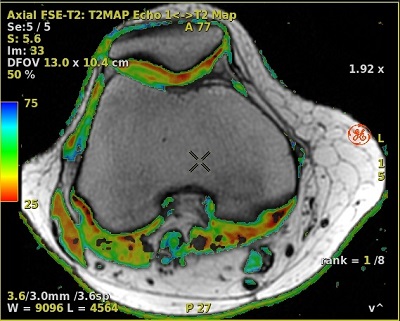

Figure 1. T2 Map parametric image fused to knee anatomical image

7. If desired, fuse the map with a source image. For details, see Fuse images/maps.